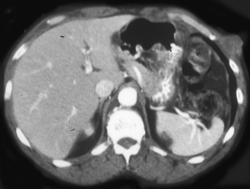

Diagnosis

Cystic Lesions Femur Possibly Due to Old Trauma